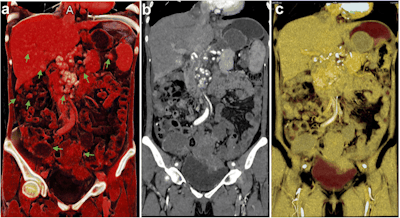

Traditional volume-rendered CT scans did not effectively distinguish the metastases from the surrounding gastrointestinal tract. Multiplanar reconstruction was able to display an overall view of the metastases, but only with minimal detail. In contrast, the cinematically rendered CT scans showed that the metastatic nodules had invaded and were deeply adhered to the colon wall. This finding led to the clinicians' recommendation against surgery in favor of chemotherapy.

In a separate case, the ultrasound exam of a 51-year-old woman with abdominal discomfort revealed a pelvic mass. Follow-up CT scans further identified multiple masses near the ovaries. Unlike with traditional volume rendering and multiplanar reconstruction, cinematic rendering of these CT scans clearly depicted the masses and showed that they could safely be removed, even though they were attached to the bladder.